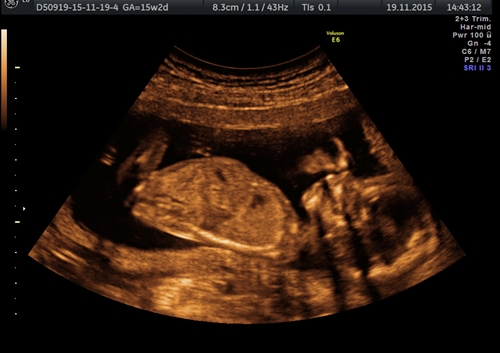

Hi :) I already know the sex of the baby but just for fun, and because there was a big doubt for the scan...

Will someone make a guess before I reveal it?

It's from 15w 2d.

Attachment 28573